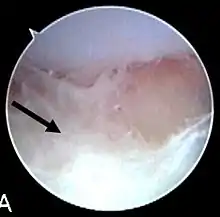

Septic arthritis as seen during arthroscopy[1] The arrow points to debris in the joint space.